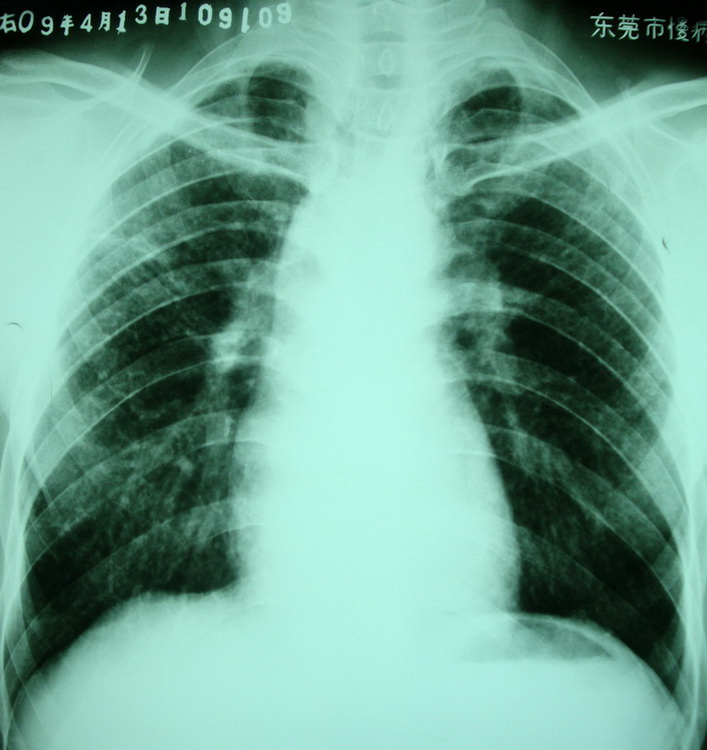

按顺序依次是:(都有粉尘职业史)

卢某,男,37岁,i+尘肺,右上肺tb?